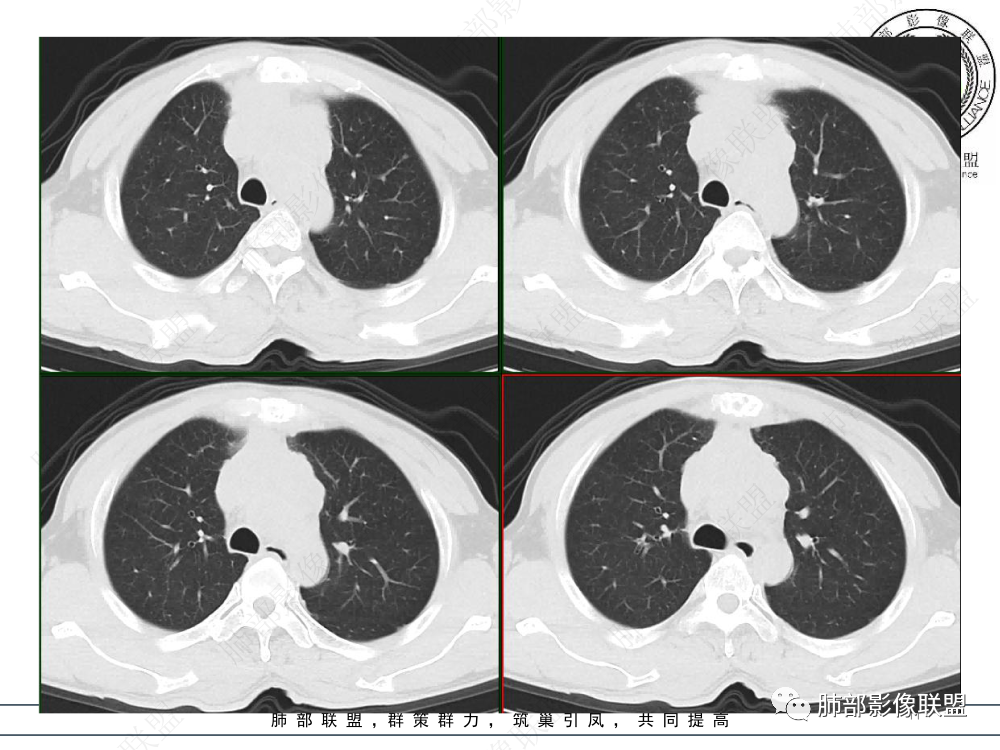

1.临床资料:中老年男性,病史较长-8个月,主诉胸痛,实验室资料:乳酸脱氢酶(LDH)升高。

2.影像表现:前上纵隔较大肿块,密度不均,形态不规则,边界不清,有结节样突起,脂肪间隙显示不清。病灶侵犯左无名静脉及上腔静脉,其中左无名静脉闭塞(胸背部侧支循环明显,亦表明回流受阻)。增强后轻中度不均强化。坏死边界欠清晰。可见心包积液,提示心包受侵犯。右侧上叶及纵隔胸膜下结节影,疑胸膜肺转移可能。胸骨柄后缘皮质不完整,疑骨质破坏(未提供骨窗及矢状位图像)。左锁骨上可见肿大淋巴结。